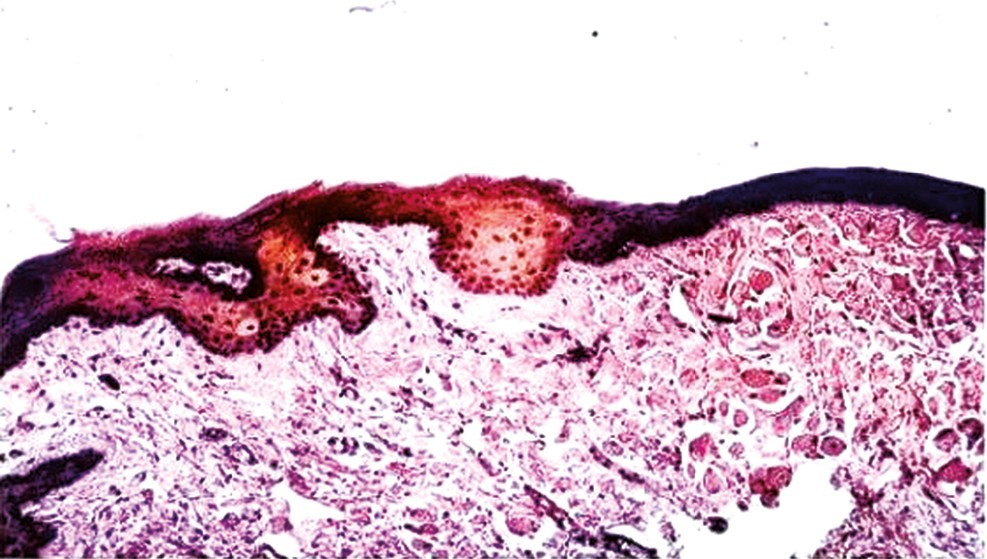

In patients with dentures fabricated from Ftorax acrylic resin, morphologic analysis of the oral mucosa under and along the denture borders revealed thinning of the epithelial layer of the mucosa, consisting of only 4–5 cell rows, and overall epithelial atrophy beneath the denture surface. Keratohyalin granules were sparse, and the granular layer appeared poorly defined. In the prickle-cell layer, hypochromic nuclei of karyopyknotic and acantholytic cells were observed, whereas basal cells were predominantly cylindrical and often in mitotic phase. The adjacent connective tissue showed segmentation into deep layers and was infiltrated with lymphohistiocytic elements (see Fig. 2). Radiographic examination demonstrated destruction of the cortical plates of both jaws, osteoporotic and dystrophic changes in the alveolar bone spurs, combined horizontal and vertical bone resorption, deep osseous pockets, structural disorganization, and focal dystrophy within periodontal structures.

Fig. 2. Morphology of the oral mucosa in patients using dentures fabricated from Ftorax acrylic resin. Hematoxylin and eosin staining; ×100. Scanning electron microscopy (SEM).